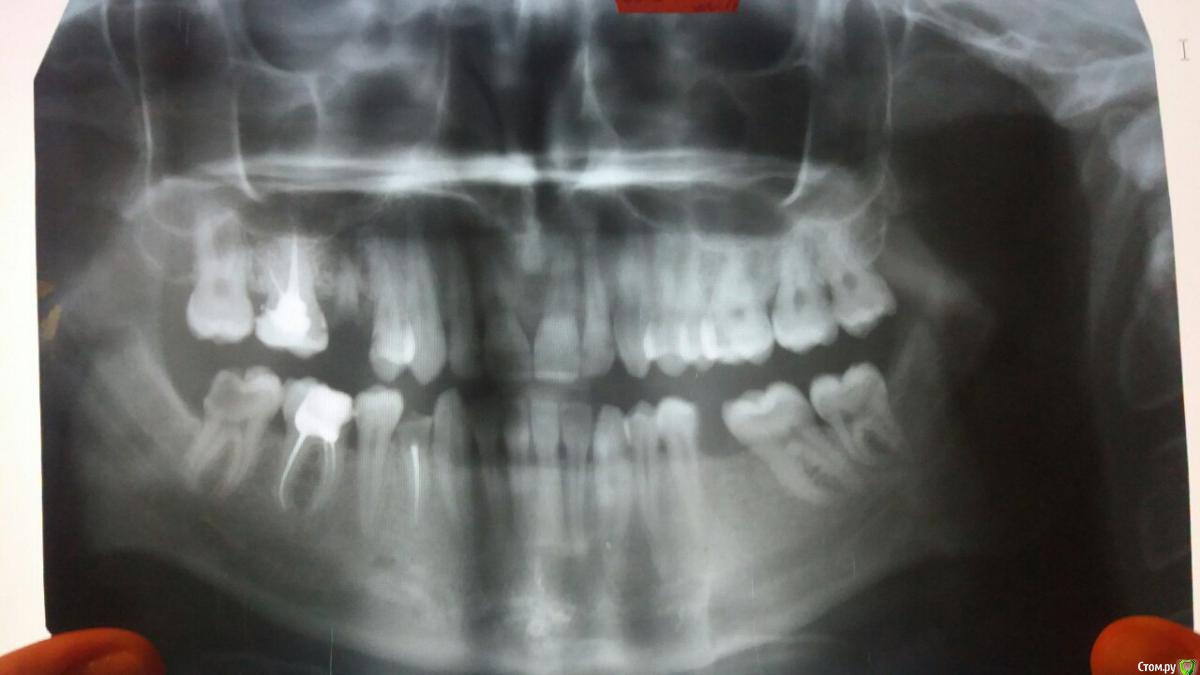

Krevetka Опубликовано 4 февраля, 2016 Поделиться Опубликовано 4 февраля, 2016 Коллеги, помогите пожалуйста с диагнозом. Или подскажите к какому специалисту направить...Есть пациент (не мой, просто вызвалась помочь ))) ) с жалобами на боль в нижней челюсти. Со слов пациента: сначала боль была в области уха, потом в нижней челюсти (под ухом), потом в области виска. боль имеет разлитый характер, пульсирующая, постоянная. Раньше болела только левая сторона, сейчас начинает болеть и правая. При жевании боль немного уменьшаеться. Утром болит меньше, вечером больше, во время физической нагрузки начинает пульсировать в ухе. пациент был на консультации в ЛОРа, челюстно-лицевого, стоматолога, ревматолога, невропатолога... точный диагноз так никто и не поставил. есть панорамный ртг (до лечения в стоматолога) Ссылка на комментарий

Елена Миллер Опубликовано 5 февраля, 2016 Поделиться Опубликовано 5 февраля, 2016 пульпит 47, обострение Ссылка на комментарий

ЕленаВалерьевна Опубликовано 5 февраля, 2016 Поделиться Опубликовано 5 февраля, 2016 а мне и 4.6 не нравится, ну и 4.7 наверняка пульпит, согласна с Еленой Миллер. и даже по описанию жалоб классические пульпитные боли. Ссылка на комментарий

annda Опубликовано 5 февраля, 2016 Поделиться Опубликовано 5 февраля, 2016 (изменено) Болит левая сторона от обострения пульпита в 47?Миофасциальная боль,триггерные точки надо искать в шее и жевательных мышцах.Справа пульпитный зуб есть.Болеть имеет право. Изменено 5 февраля, 2016 пользователем annda Ссылка на комментарий

Krevetka Опубликовано 5 февраля, 2016 Автор Поделиться Опубликовано 5 февраля, 2016 панорама была сделана до лечения у стоматолога. со слов пациента, ротовая полость сейчас полностью санорованакак Вам сказать.... полностью санирована.... Сегодня еще с ним списывались, выложеная панорама - это панорама "до", панорама "после" отличается тем, что на 38, 45, 46, 47 стоят пломбы. Эндо в 37 не делали, в 47 - пациент сам не знаетНачинает болеть правая сторона-сомневаюсь, что в 47 вылечен пульпит. В 38 тоже пульпит под вопросом.... 80% таких болей имеют стоматологическую этиологию. рекомендовала пациенту провести нормальную санацию полости рта. думаю, он в эти 80% попадает. если же нет-по рекомендации невропатолога- рентген сустава, возможно консультация нейрохирурга, возможно мрт головы. как-то так Ссылка на комментарий